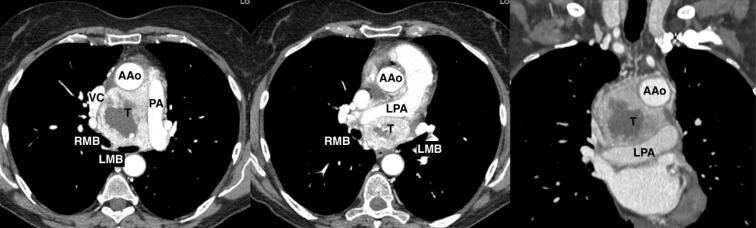

无功能性中纵隔副神经节瘤是一种罕见病。我们描述了一例 67 岁女性的病例,她在胸部 CT 和 18F 氟脱氧葡萄糖正电子发射断层扫描后,通过支气管内超声经支气管针吸术确诊为大纵隔副神经节瘤。肿瘤长约 9 厘米,位于上腔静脉和升主动脉后部之间,压迫左心房、气管和左主支气管,后方环绕右肺动脉。单孔右侧视频胸腔镜活检未得出结论,并发严重出血,但已得到控制。手术通过经胸腔经心包入路进行,然后进行心肺旁路和升主动脉切除,这样可以很好地暴露并更好地控制大血管和心脏。除左侧声带麻痹外,肿瘤完全切除,无围手术期并发症。12 个月后,患者已无疾病,全身状况良好。

A non-functional middle mediastinal paraganglioma is a rare entity. We describe a case of a 67-year-old woman with a diagnosis of a big mediastinal paraganglioma by endobronchial ultrasound transbronchial needle aspiration after chest CT and 18F-fluorodeoxyglucose positron-emission tomography. The nine centimeter in length tumor was located between the superior vena cava and the posterior portion of the ascending aorta, compressing the left atrium and the trachea and main left bronchus, posteriorly, surrounding the right pulmonary artery. Uniportal right video-thoracoscopic biopsy was unconclusive and complicated by severe hemorrhage, however controlled. Surgical resection was performed via a trans-sternal trans-pericardial approach followed by cardiopulmonary bypass and ascending aorta resection which allows an excellent exposure and greater control of great vessels and heart. Complete resection of the tumor was achieved without perioperative complication except for the left vocal cord palsy. Twelve months late the patient is disease free and in good general conditions.